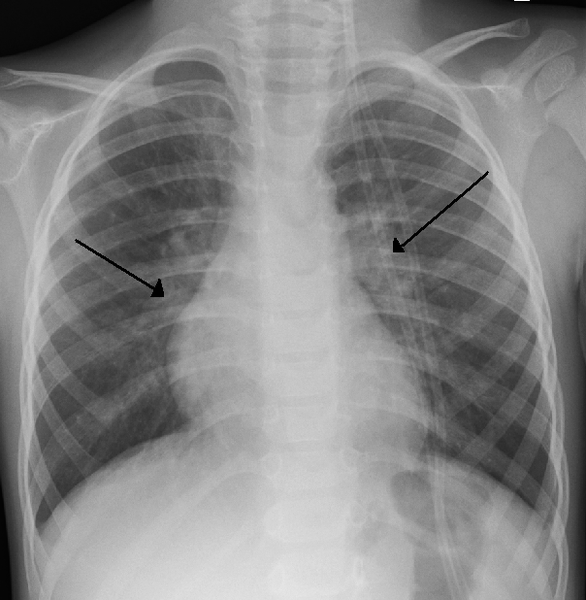

Viirus infitseerib hingamisteid ning indutseerib hingamisteede epiteelis rakkude fusiooni ehk süntsüütiumide tekke. Nakatunud rakke ründab organismi immuunsüsteem. Bronhide ja bronhioolide limaskesta nekroosil tekivad “korgid” (lima, fibriin, nekrootiline kude), mistõttu on võimalik hingamisteede ummistumine.

Infektsioon võib olla erineva raskusastmega – kõige sagedamini tekib nohu või mõni muu hingamisteede kerge nakkuse kliiniline pilt. Samas võib tekkida ka bronhiit, bronhioliit või pneumoonia.

Bronhioliit võib viia surmale enneaegsed

vastsündinud, kopsuhaiged, immuundefitsiidiga isikud hingamisteede ummistumise

ja hapnikupuuduse tõttu.